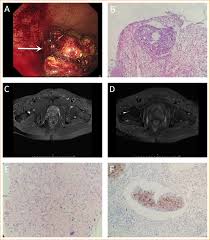

Is It Ovarian Cancer Or Irritable Bowel Syndrome Ibs Everyday Health

Is It Ovarian Cancer Or Irritable Bowel Syndrome Ibs Everyday Health from images.everydayhealth.com

Another condition that can be misdiagnosed as cancer in the colon is hemorrhoids. Potent, yet safe — you & your loved one can beat cancer too — learn more here! Is there a connection between colon cancer and ibs? Apr 01, 2020 · irritable bowel syndrome (ibs) is a chronic disorder of the large intestine, also known as the colon. Jul 01, 1999 · in the retrospective part of the study, 27 patients were diagnosed with diverticulitis and 31 were diagnosed with colon cancer. Colorectal cancer may be mistaken for inflammatory bowel diseases (ibds) such as irritable bowel syndrome (ibs) and ulcerative colitis. What kind of cancer is mistaken for bowel disease? Colorectal cancer may also be misdiagnosed as hemorrhoids, or piles.